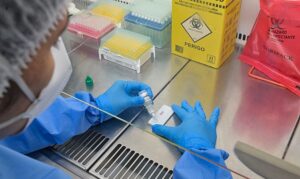

OMS descarta indícios de “surto maior” de hantavírus

Até o momento, foram relatados 11 casos da doença, incluindo 3 óbitos

A infecção por hantavírus pode causar síndrome respiratória aguda e não possui vacina nem tratamento específico